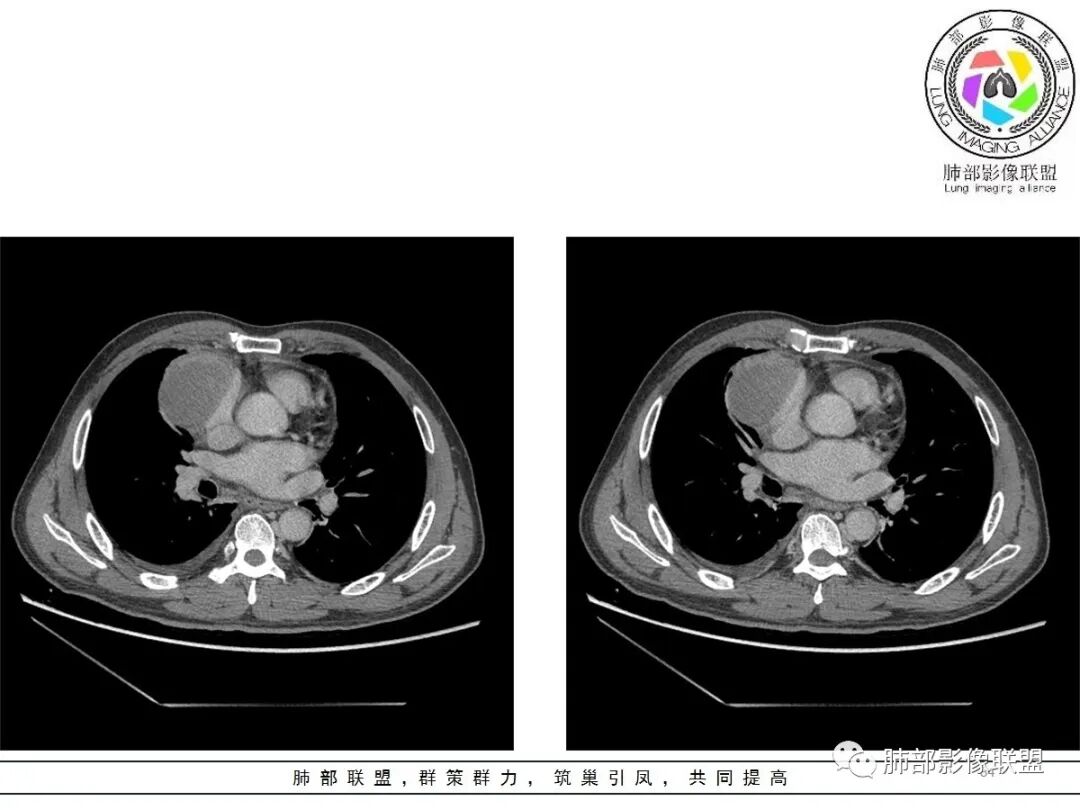

一切∮随缘:定位肺外,病变位于右前纵隔,与肺部交接面清晰,有胸膜尾征,心包局部受压,部分包绕主动脉血管,平扫密度均匀,形态规则,膨胀性生长,增强扫描壁有强化,内容物无明显强化,考虑1:淋巴瘤2:胸腺瘤3:神经鞘瘤4:支气管囊肿

亚东:前纵隔囊实性肿物,形态尚规则 ,与心包分界不清,内可见小气泡,嚢内平扫密度低,强化不明显,囊壁强化,右胸腔积液,淋巴结肿大不明显,化验白细胞高,支持囊肿伴感染。

小强:前纵隔肿块,边缘模糊,其内有点状气体影,环形强化(肉芽肿?),心包胸膜受累,疾病谱:胸腺瘤(一般是侵袭性胸腺瘤累计心包,胸膜,强化不符合)淋巴瘤,生殖细胞瘤(年龄,AFP不高不负),考虑畸胎瘤,囊性畸胎瘤合并感染,边缘模糊,累计心包胸膜,3.19病变进展,胸腔积液,可能有破溃

修*:前纵隔偏右侧肿物,点状钙化,轻度强化,伴胸腔积液,考虑胸腺瘤B2型。

王秀仙:右侧前纵膈肿块,密度不均,局部边缘可见点状钙化,其内可见点状低密度,与纵膈血管间脂肪间隙消失模糊,右侧胸腔积液,考虑纵膈畸胎瘤或皮样囊肿破裂。鉴别胸腺鳞癌。

必有路:老年人,右前纵隔占位,发病前纵隔脂肪干净,突发起病伴胸痛,白细胞增高病灶整体密度较为均匀,内有点状脂肪密度,位置个人觉得理胸腺区有点偏下,大部分囊性为主1、胸腺瘤伴突发梗死  突发起病,老年男,不支持点,位置偏下,囊变坏死太彻底,右侧胸廓内动脉没有增粗(实性肿瘤,往往会有间接供血增粗)倾向支持囊性病灶合并破溃感染2、囊性畸胎瘤伴破溃  影像上可以支持,脂肪含量比较少,发病年龄不太支持3、 皮样囊肿 可以有脂肪密度4、 支气管囊肿 理论上胸廓内都可以发生,肺内 后纵隔多见 张力大 圆5、心包囊肿  中纵隔更为多见综上,皮样囊肿>囊性畸胎瘤>胸腺瘤

肿瘤样病变破裂所致纵隔炎应该没错

南边:肿瘤或肿瘤样病变破裂所致纵隔炎,这是大方向

结果:符合B型胸腺瘤伴出血,坏死囊性变,局部脓肿形成